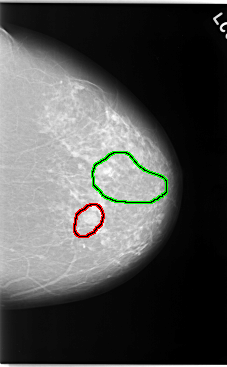

C_0044_1.LEFT_CC

FILE: C_0044_1.LEFT_CC.OVERLAY

TOTAL_ABNORMALITIES 2

ABNORMALITY 1

LESION_TYPE MASS SHAPE OVAL MARGINS CIRCUMSCRIBED

ASSESSMENT 3

SUBTLETY 5

PATHOLOGY BENIGN

TOTAL_OUTLINES 1

BOUNDARY

ABNORMALITY 2

LESION_TYPE CALCIFICATION TYPE FINE_LINEAR_BRANCHING DISTRIBUTION SEGMENTAL

ASSESSMENT 5

SUBTLETY 4

PATHOLOGY MALIGNANT